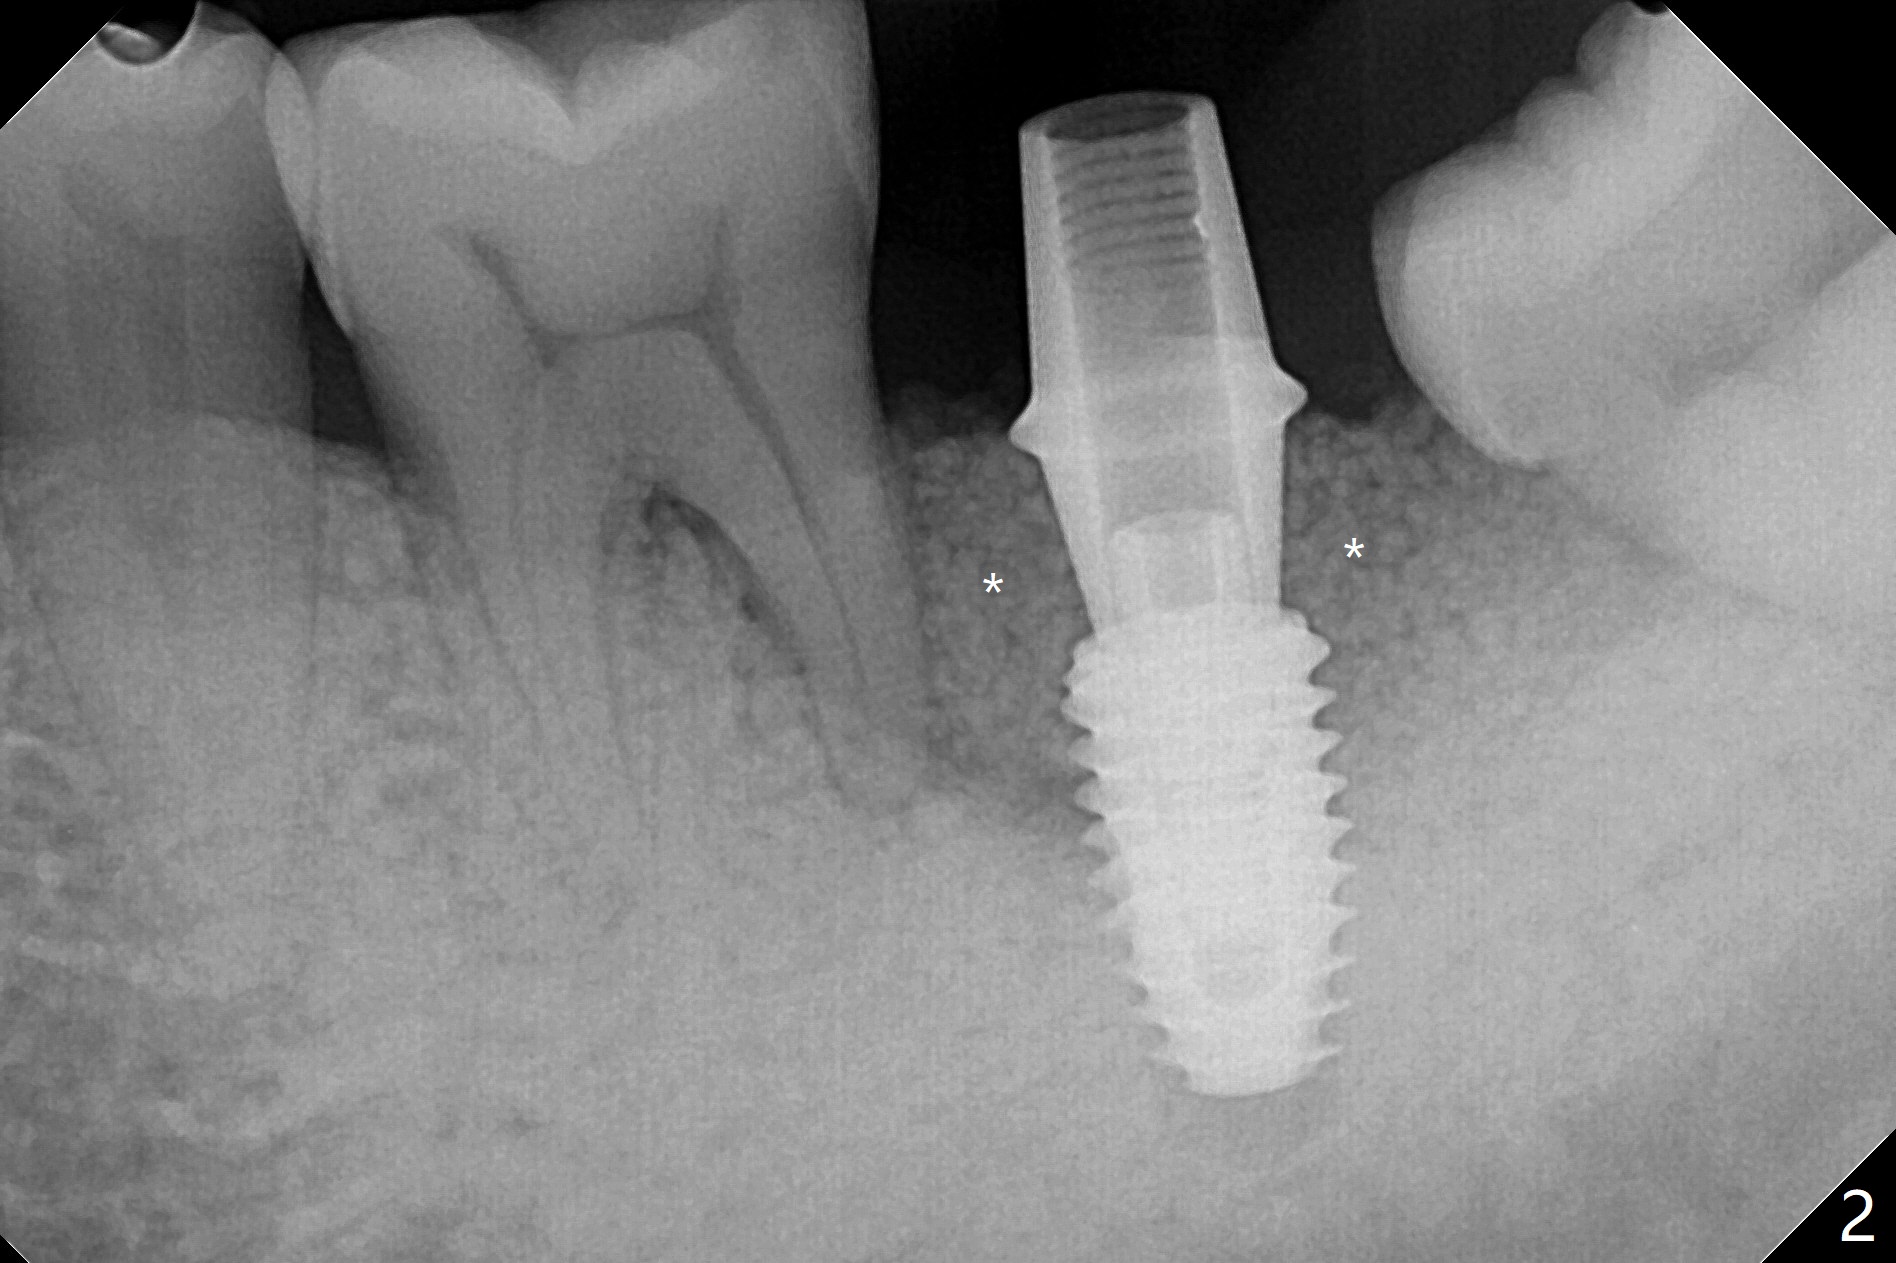

植骨成功必须有两个成分,软硬组织,牙龈提供血运和口袋,而硬组织防止骨粉塌陷。例如即刻植体和基台是可靠,免费(与钛网而言)硬性支撑,今天添加另外一个天然硬性支撑,那就是预后不是很好邻牙。40岁男左下7严重骨质吸收,颊侧,舌侧骨板缺失,骨粉(红色圆圈)将放置6远中,让它发挥余热。8暂时保留,这样7导板稳定些,植入更准确(图一),之后拔除8。结果术中改变计划,得寸进尺,也想保留8,理由骨粉更稳定(图二:*),尤其是远中。6,8牙根面做了刮治。为了证实基台完全就位,又拍摄一张咬翼片(图三),这时植体螺纹清晰。植体与基台之间有两个重要接触部分,第一,图三空箭头,两者必须完全融合(必须没有间隙),理论上可以形成冷焊接(cold welding);第二,短箭头,公母六角形(hex)相接,之间有间隙。如果初步稳定性低,选择愈合基台,与植体交接也必须有X光片验证,两者之间不应该有间隙。如果有间隙,愈合过程,愈合基台很可能脱落,造成病人不安,增加我们工作量,破坏临床进展。图三:术后即刻。术后5.5月(图四)骨粉丧失许多,牙冠外面使用牙周敷料或者直接使用树脂敷料,可能会减少骨粉流失。临床上智齿近中好像没有明显倒凹,取模,估计以后食物坎塞不会太严重。术后6月(牙冠粘固,拧紧25Ncm,图五),螺纹没有暴露。